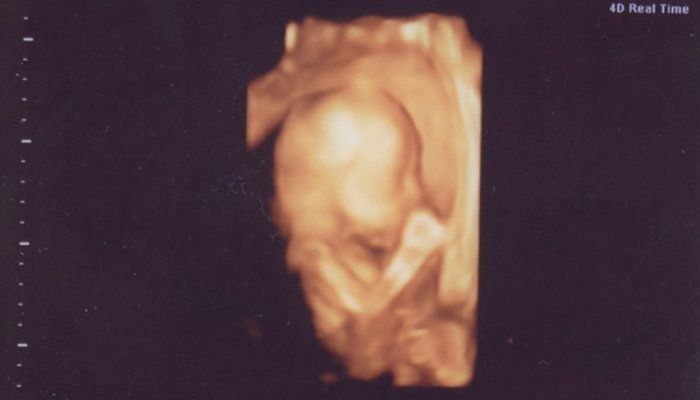

セイコさんの妊娠22週目のエコー写真 初めての4D!感動です

里帰り出産のため、実家の方の病院へ予約に行きました。そちらの病院だと4Dがあるので、初めて見ることができました。すごくリアルで感動です。この子がおなかの中いるのかと、しみじみと愛しく思いました。

同じ日ですが、相変わらずのカメラ目線です。歯みたいなものがはっきり映っていますが、歯ではなく歯茎らしいです。助産師さんがメインで出産を行っている産院なので、高齢初産の体調管理や体力増強について厳しく指導を受け、頑張ろうと思いました。産院で開催している母子学級にも参加し、様々な体調の変化についても勉強しました。